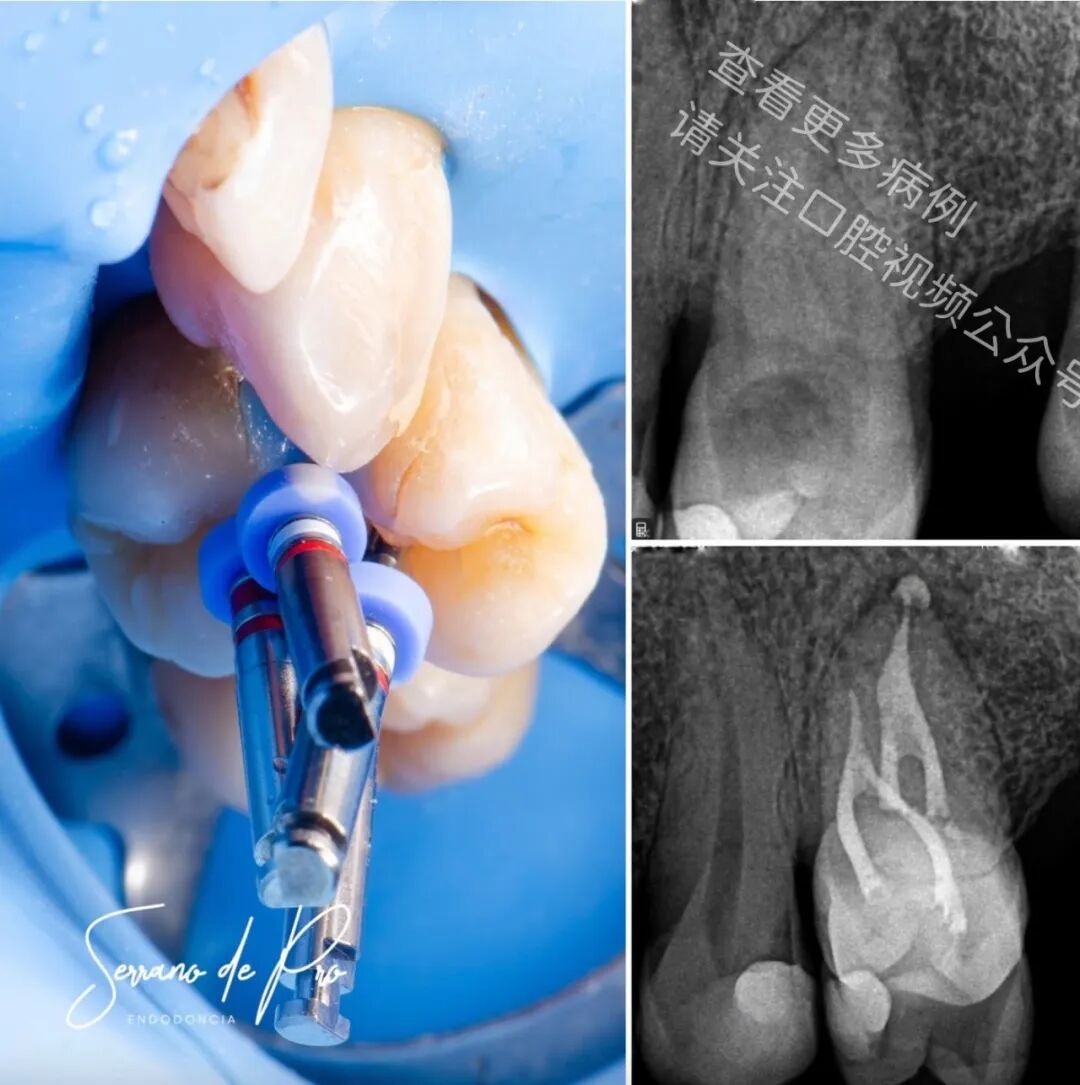

这是一个非常奇特的病例,24号牙和25号牙并非处于它们的正常位置,而是并排生长,拍出的X光片十分惊人。能如此清晰地看到根管充填的细节可不是每天都有的事。25号牙牙髓坏死,24号牙则患有严重的牙髓炎。

两颗牙都使用了来自FKG Iberia公司的Raceevo锉预备到30.04的锥度,并用Avalon Biomed公司的Neosealer Flo封闭剂以及Zarc4endo公司的产品配合WaveOne垂直加压(WVC)技术进行根管充填。

由于患者的病史,25号牙因存在禁忌证而未被拔除。